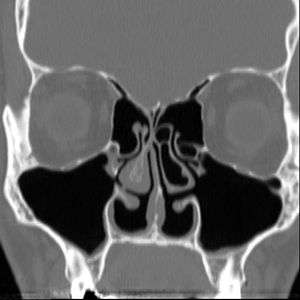

| Altered nasal anatomy after bilateral subtotal inferior turbinectomy | |

There are no objective physical examination findings that definitely diagnose ENS.[1] Generally, one or more turbinates may be reduced or absent when viewed in medical imaging or via endoscope with no sign of physical obstruction, the mucosa will be dry and pale, and there may be signs of secondary infection.[1]